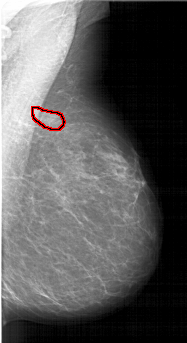

A_1610_1.LEFT_MLO

LEFT_MLO LINES 6421 PIXELS_PER_LINE 3601 BITS_PER_PIXEL 12 RESOLUTION 43.5 NON_OVERLAY

FILE: A_1610_1.RIGHT_MLO.OVERLAY

TOTAL_ABNORMALITIES 1

ABNORMALITY 1

LESION_TYPE MASS SHAPE ASYMMETRIC_BREAST_TISSUE MARGINS ILL_DEFINED

ASSESSMENT 4

SUBTLETY 3

PATHOLOGY BENIGN

TOTAL_OUTLINES 1

BOUNDARY